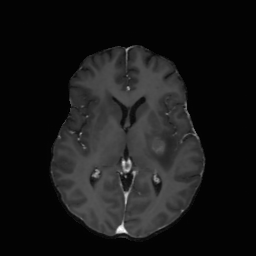

| non-CE T1w (Input) | Residual U-Net (PM) | RF Baseline | PMRF (ours) | CE T1w (GT) |

We qualitatively evaluate the top-performing Residual U-Net (Posterior Mean), RF baseline, and PMRF models (with a patch-overlap of 32 for all and integration steps for the RF baseline as well as the PMRF model) on the held-out test set. For a set of representative cases, Figure 3 compares the non-CE T1w input, Res. U-Net (equivalent to PM), RF baseline, our two-stage PMRF, and the ground truth CE T1w image. Example 1 depicts a metastases patient, example 2 a high-grade glioma patient, and example 3 a meningioma patient. Across these test cases, the Res. U-Net output accurately localizes lesions and captures their overall enhancement intensity but appears overly smooth, and muted in rim heterogeneity and fine texture. The Stage 2 PMRF refinement consistently sharpens lesion boundaries, reinstates subtle vascular and margin details, and restores characteristic enhancement patterns, yielding synthetic images nearly indistinguishable from true post-contrast scans. However, Stage 2 can only refine what the posterior-mean predictor already suggests. If a subtle rim, micro-metastasis, or vessel enhancement is entirely suppressed in Stage 1, Stage 2 has no signal to resurrect it; its perturbations stay within a narrow neighborhood of the Stage 1 output. In contrast, the RF baseline directly predicts the CE signal from the perturbed non-CE image. However, this comes with the limitation of not predicting the CE strength faithful or missing subtle details as in examples 2 and 3.